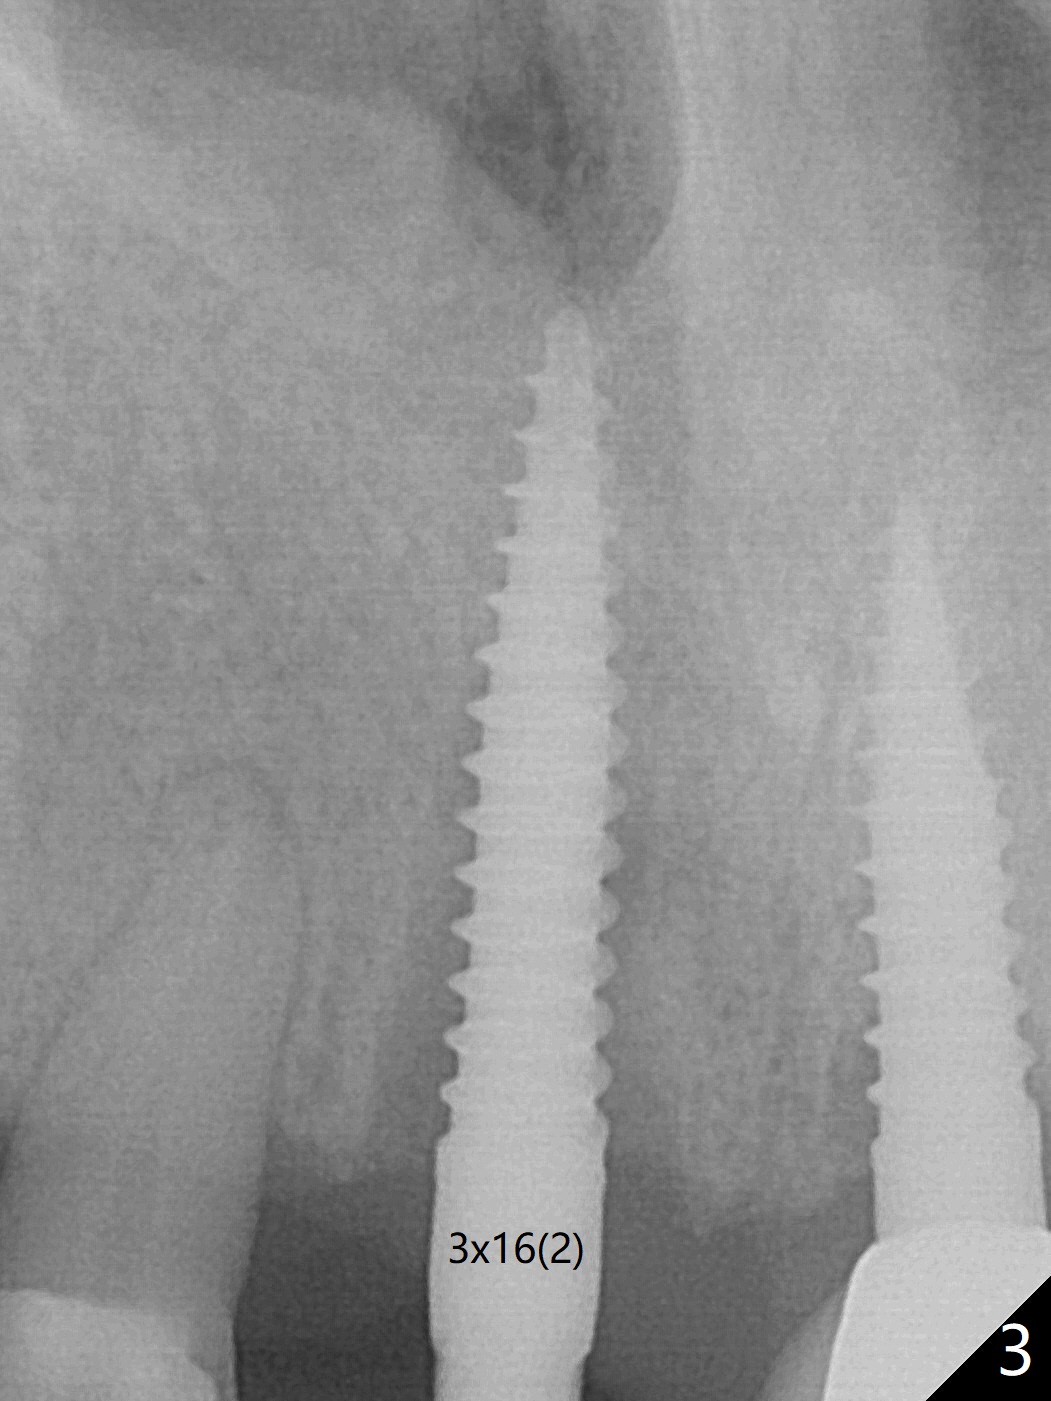

Reanalysis of preop CBCT shows a longer implant (3x16mm, green) to be placed palatal should be able to solve buccal plate bone loss associated with the previous 3x14 mm one at #8 (Fig.1). After crown/implant removal (with ease), a new palatal osteotomy is initiated flapless with 1.2 mm drill for 16 mm (palatal gingival margin, Fig.2). Following 1.5 mm drill for ~ 17 mm, a 3x16(2) mm 1-piece implant is placed >40 Ncm (Fig.3). After bone graft through limited access and abutment preparation, an immediate provisional is fabricated with clearance. The provisional dislodges repeatedly, mainly due to palatal perforation. It gets lost while the patient travels to his home country. Although there seems to be bone loss around the implant 2.5 months postop (Fig.4), the gingiva looks healthy. A new provisional is fabricated without impression. Because of short vertical height and small abutment diameter as well as bruxism, the provisional easily dislodges. The patient will return for impression 4 months 10 days postop. The bone loss remains 4 months postop when impression is taken (Fig.5).